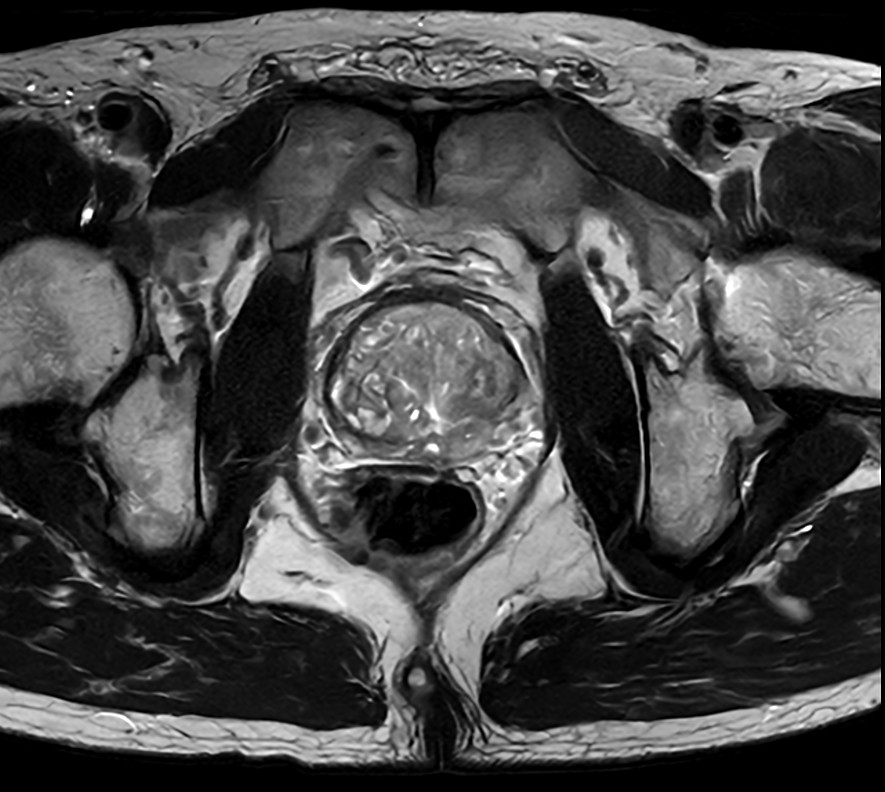

Fast Prostate imaging with SmartSpeed Precise

Kumamoto Chuo Hospital Japan